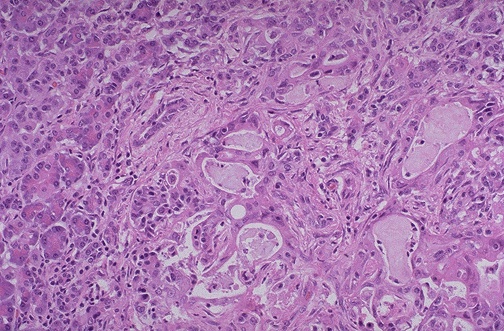

At high magnification, the microscopic appearance of an adenocarcinoma of the pancreas is seen. At the left can be seen

normal pancreatic acini

, but the neoplasm is composed of

small irregular glands

.